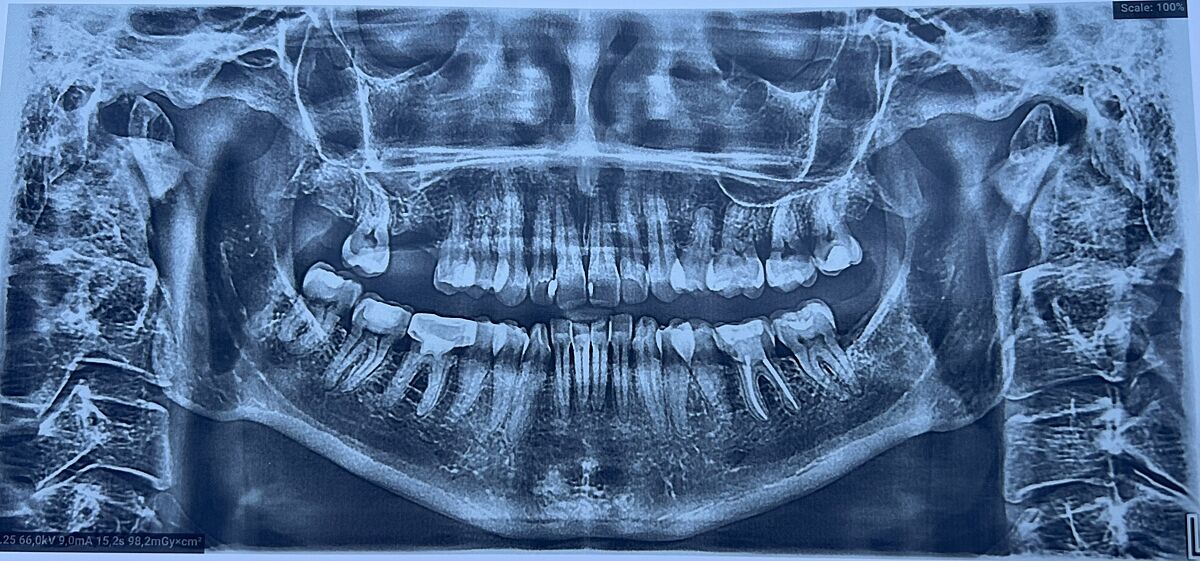

Болить ліва сторона голови, 2 місяця як вирвали зуб

Два місяця як вирвали шістірку, почала боліти вся ліва сторона, болить де був зуб, болить вухо, око болить. Від болю допомагає полоскання хлогекседином або пшикалки від горла. Лікар який виривав зуб не баче що болить. Зробила сама знімок, може хтось може читати знімки де може бути запалення. Дякую